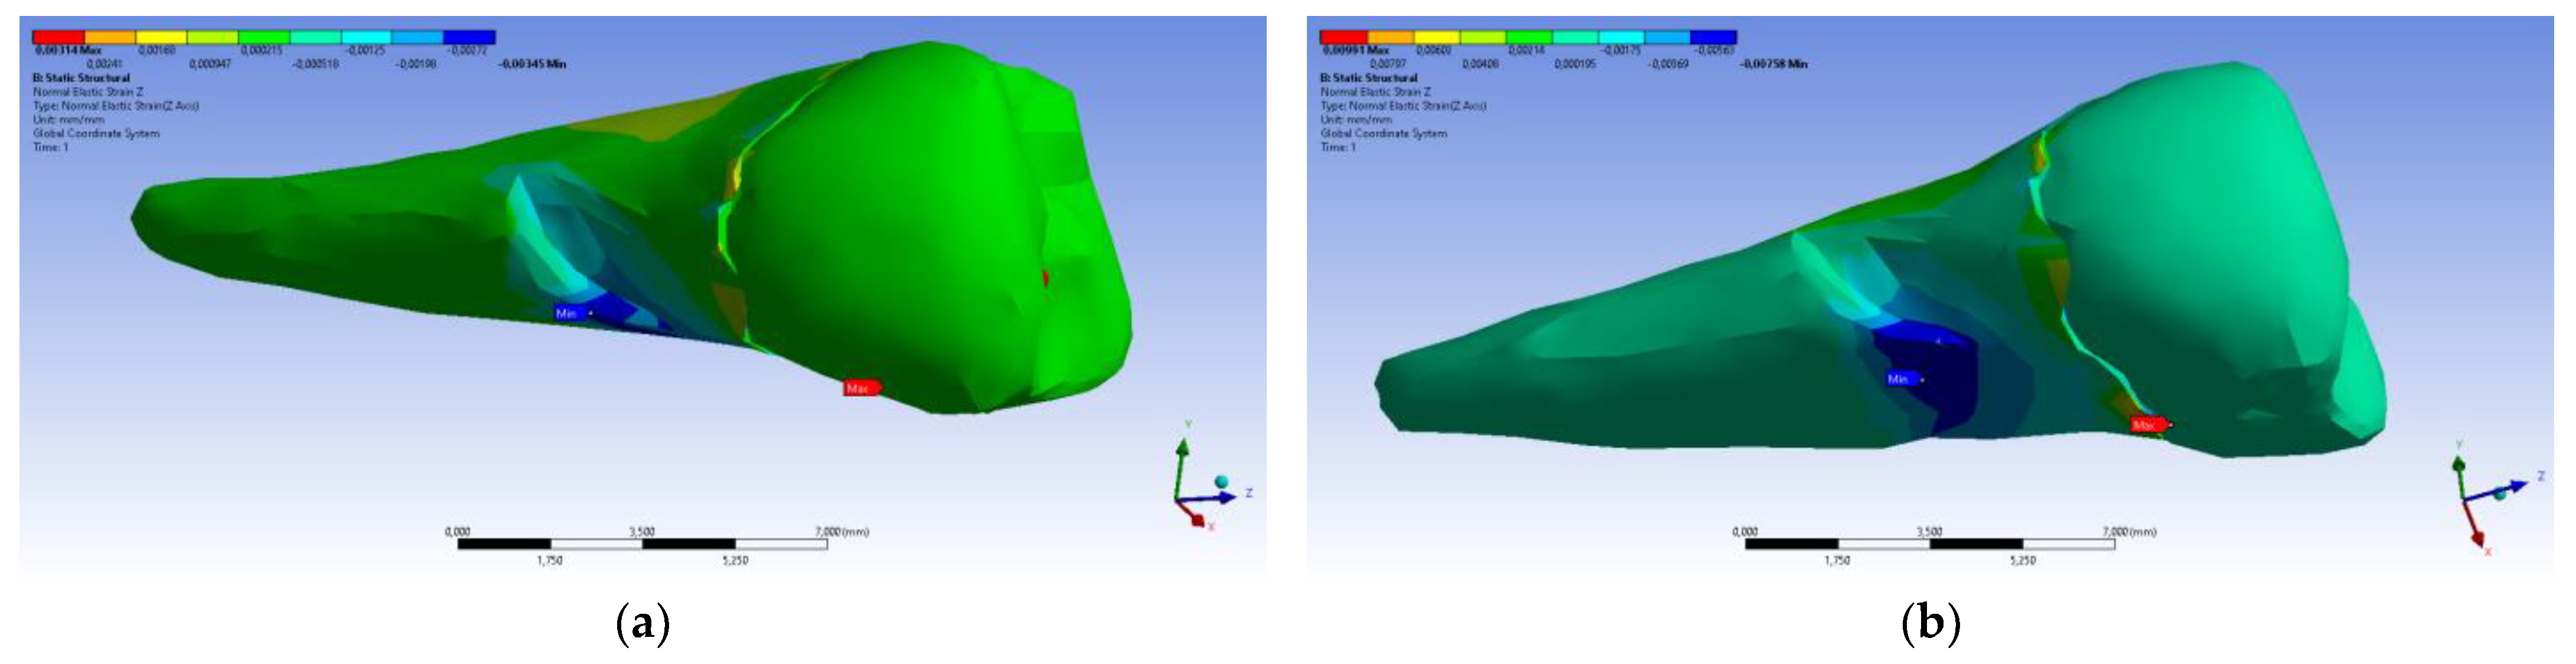

3. Finite Element Analysis (FEA) of Mandibular Right Premolars

| Maximum Tangential Stress | Main Elastic Relative Deformation | Main Maximum Elastic Relative Deformation | Main Minimum Elastic Relative Deformation | Maximum Tangential Elastic Relative Deformation | Relative elastic Normal X Deformation | Relative Elastic Normal Y Deformation | Relative Elastic Normal Z Deformation | Relative Elastic Tangential XY Deformation | Relative Elastic Tangential YZ Deformation | Relative Elastic Tangential XZ Deformation | |||

| Minimum | 5.4 × 10−7 MPa | 6.36 × 10−11 mm/mm | −1.33 × 10−5 mm/mm | −1.05 × 10−2 mm/mm | 7.6 × 10−11 mm/mm | −2.26 × 10−3 mm/mm | −1.43 × 10−3 mm/mm | −3.45 × 10−3 mm/mm | −2.81 × 10−3 mm/mm | −4.09 × 10−3 mm/mm | −7.93 × 10−3 mm/mm | ||

| Maximum | 143 MPa | 1.33 × 10−2 mm/mm | 9.66 × 10−3 mm/mm | 1.09 × 10−5 mm/mm | 2.01 × 10−2 mm/mm | 1.37 × 10−3 mm/mm | 1.89 × 10−3 mm/mm | 3.14 × 10−3 mm/mm | 6.23 × 10−3 mm/mm | 1.65 × 10−2 mm/mm | 3.13 × 10−3 mm/mm | ||

| Minim. in | Cementum | Cementum | Enamel | Cementum | Cementum | Cementum | Cementum | Cementum | Cementum | Cementum | Cementum | ||

| Maxim. in | Cementum | Cementum | Cementum | Cementum | Cementum | Cementum | Cementum | Enamel | Cementum | Cementum | Cementum |